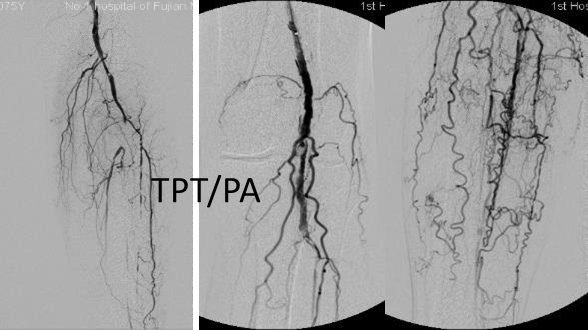

各分支 CTO 解剖特点

三大主要分支的CTO近端与远端常见位置:

总体特点:

膝下通常有单个或数个可见的流入道;

病变常为单个或多个CTO组合,总长度可达20cm;

部分患者存在踝上交通动脉或完整的踝下足底弓,为逆向开通提供可能。